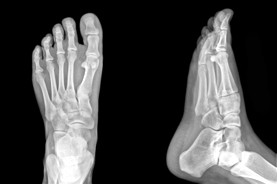

Foot Doctor Calgary & Foot Pain Specialists

The Foot Institute is an association of Calgary Doctors specializing in the medical treatment of the foot and ankle, and is one of the largest groups of foot specialists in Alberta.

The Calgary Foot Institute is dedicated to the medical and surgical treatment of the foot. Our mandate is to provide the best possible medical, surgical and preventative treatment available for our patients. We do this by providing well-trained Doctors who are committed to treat and prevent all types of foot pain, biomechanical disorders, as well as all other problems relating to the feet.

At the Calgary Foot Institute, our Doctors are trained to specifically treat problems associated with your feet or ankles. Below are several of the most common problems that we see on a day to day basis: